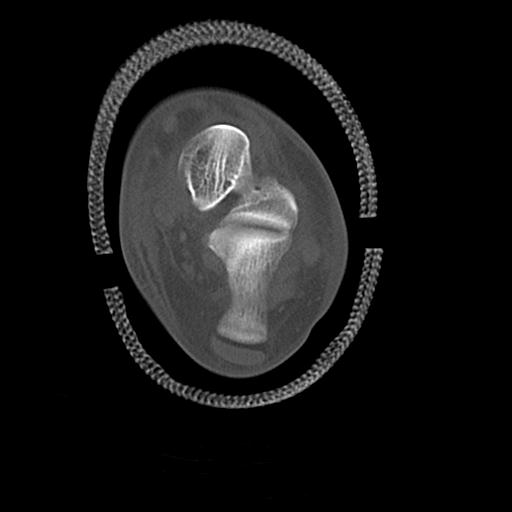

49554 3/13 膝 4R 3/16 4R 1/18 2R 78歳男性 膝蓋骨骨折